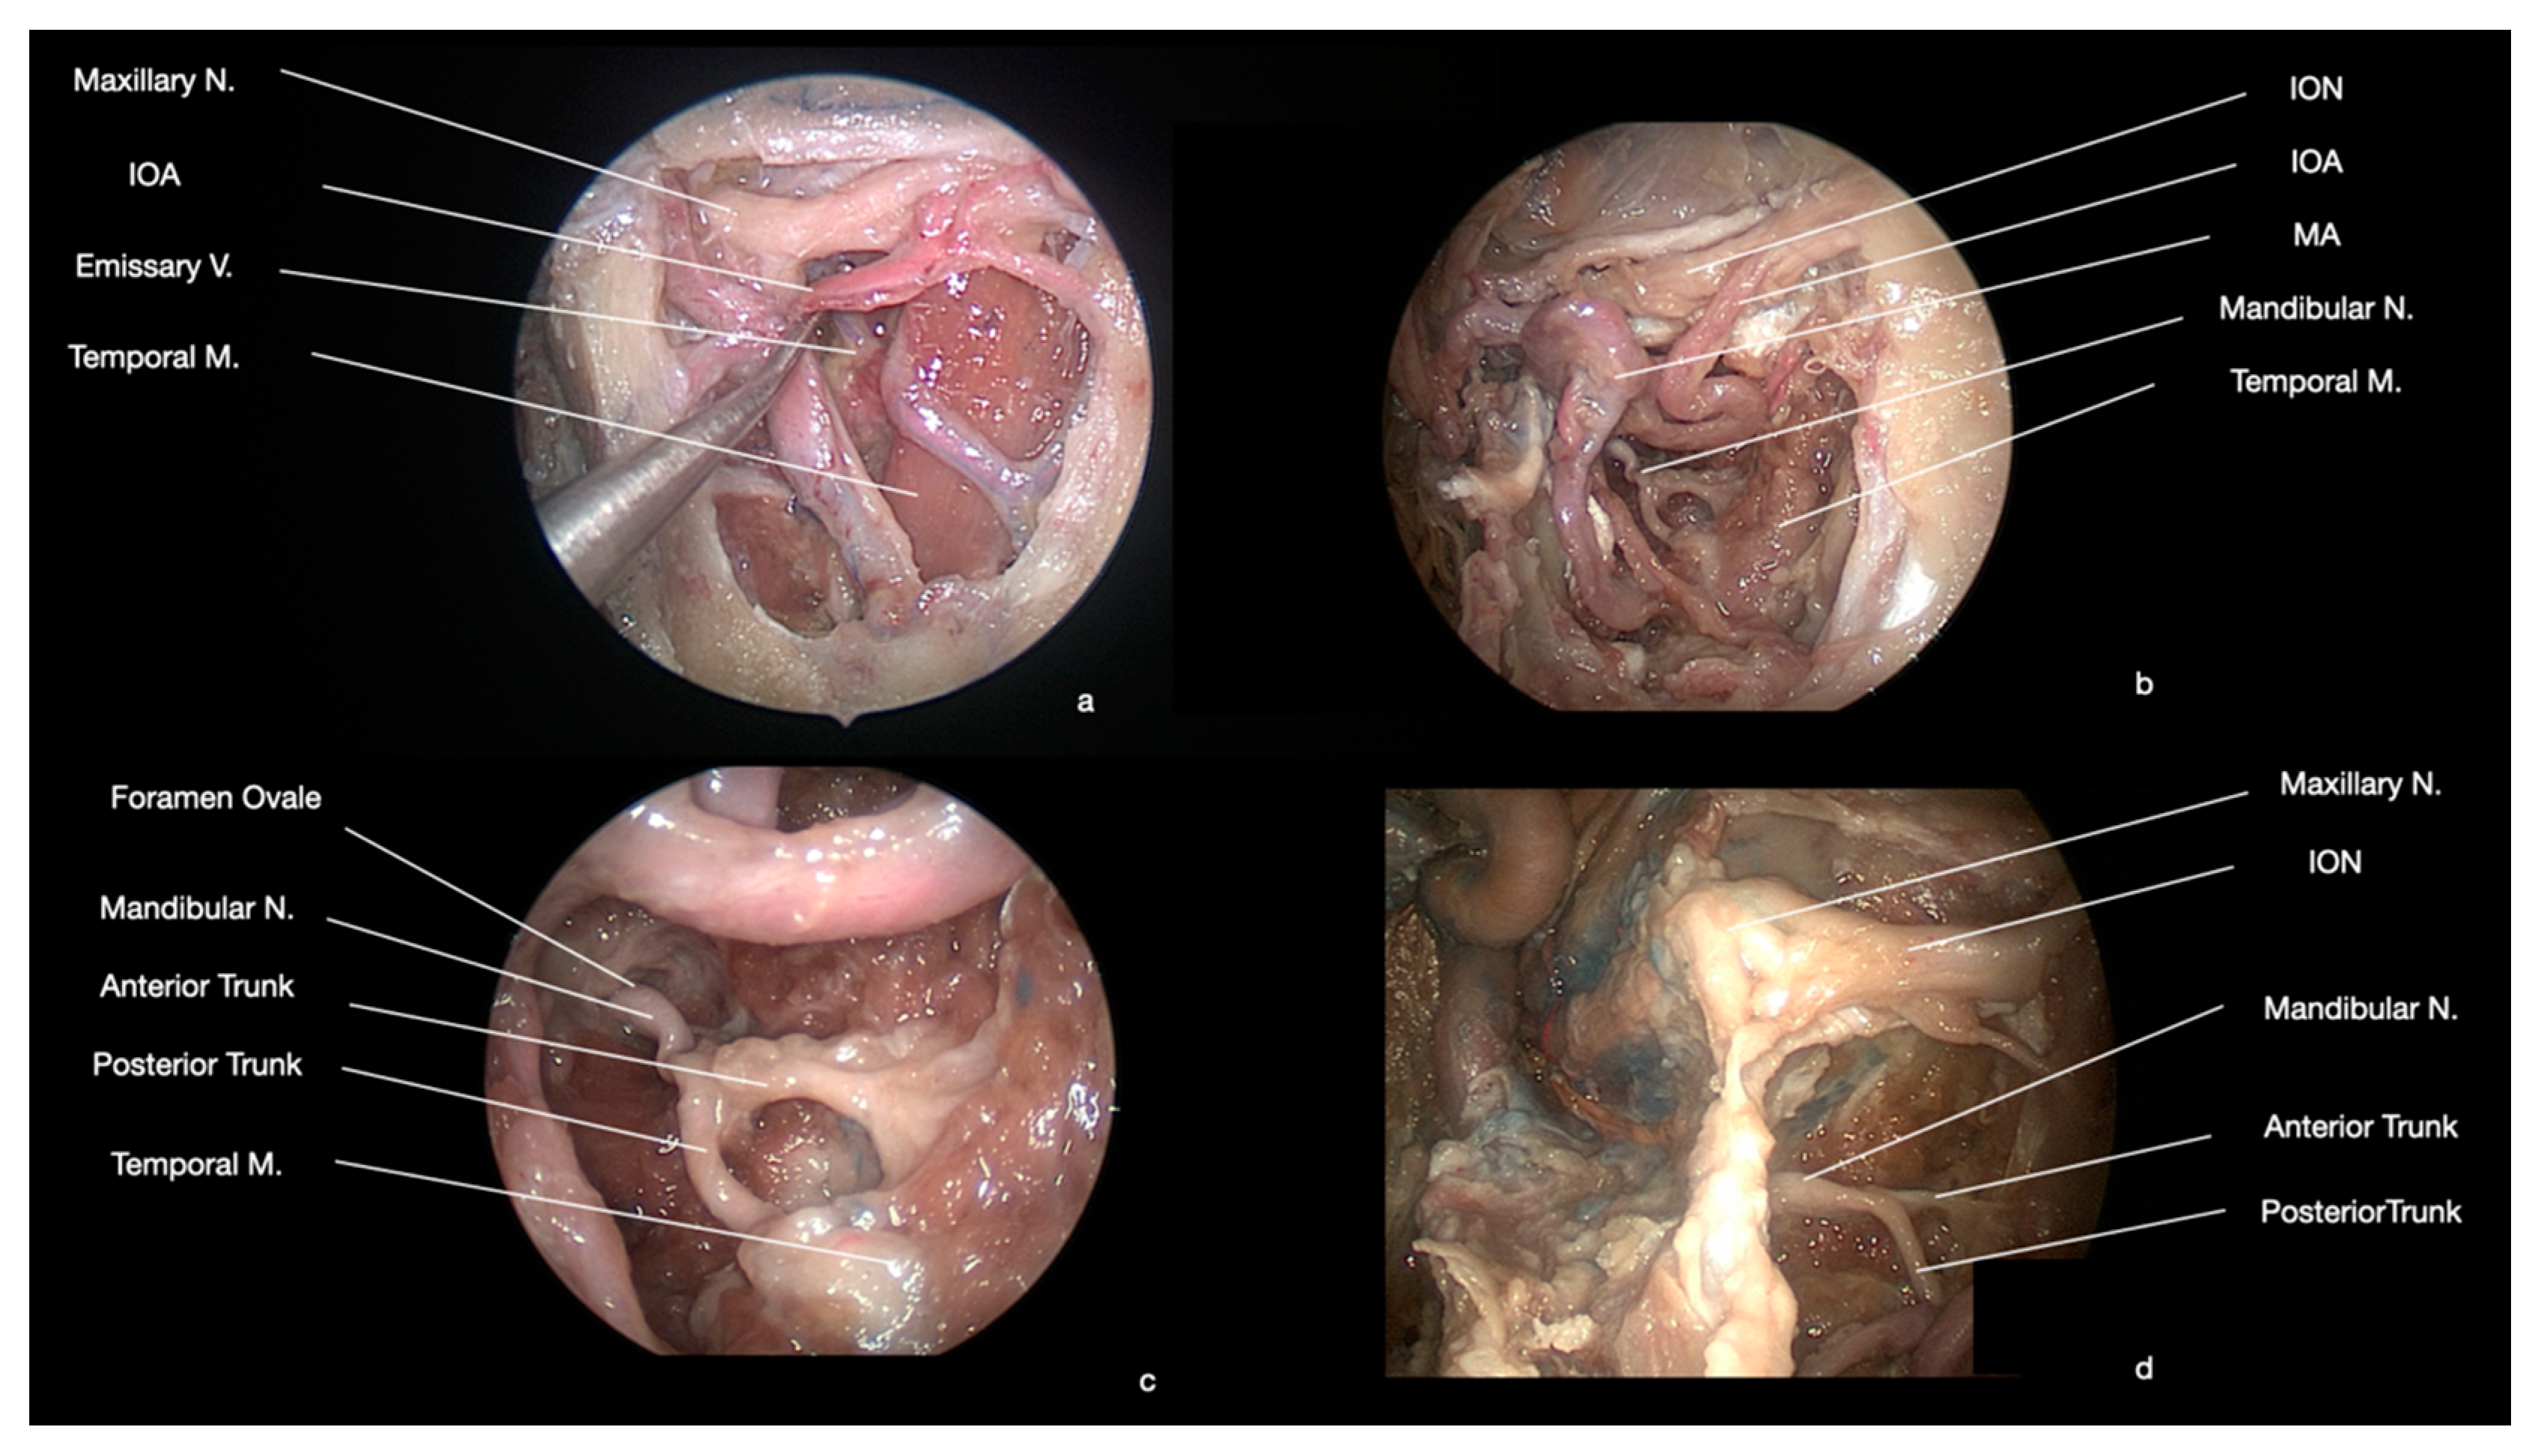

2.4. Nervous Structures